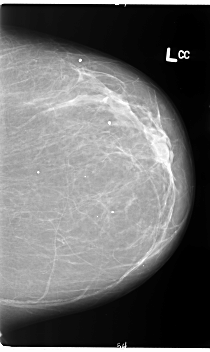

B_3109_1.LEFT_CC

LEFT_CC LINES 5976 PIXELS_PER_LINE 3568 BITS_PER_PIXEL 12 RESOLUTION 50 NON_OVERLAY